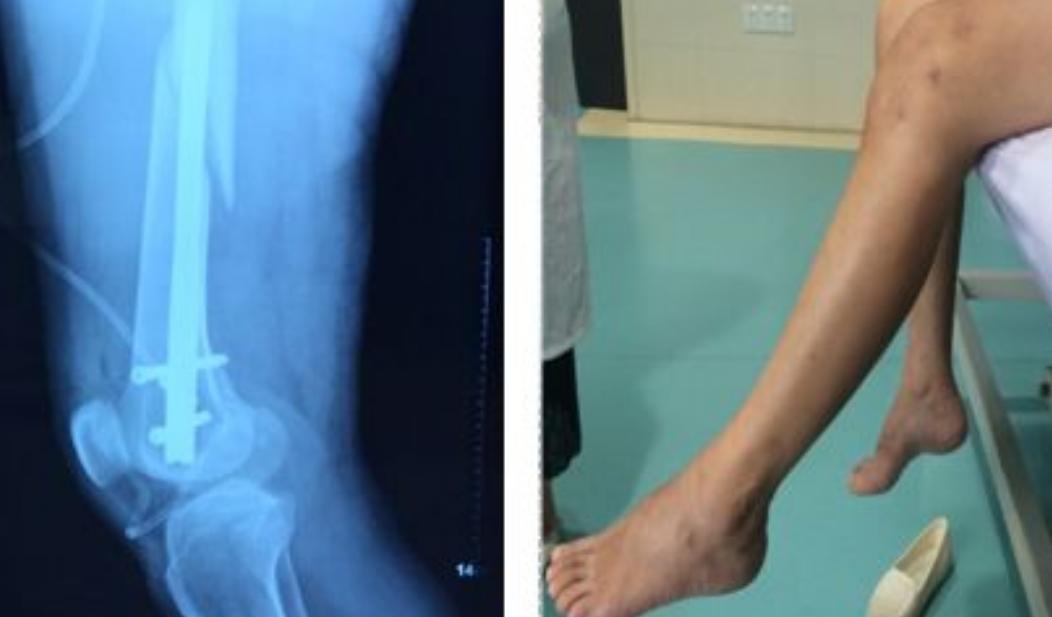

(治疗前,周阿姨的左膝关节僵硬)

家住长沙的周阿姨,不久前带孙子时在家不小心摔倒,左股骨中段完全横断斜行骨折,骨折端移位严重。

手术后,周阿姨在家静养了2个月,伤口愈合很好,本以为就好了,但是一下地,周阿姨发现左膝关节僵硬,根本就弯不了。

(康复后,周阿姨膝关节可以随意弯曲)

经过传统康复和现代手法中西结合系统治疗两个月,周阿姨走路、下蹲、上下楼梯不再困难,膝关节可以随意弯曲,行动自如,僵硬的膝关节又重新“活”了起来。